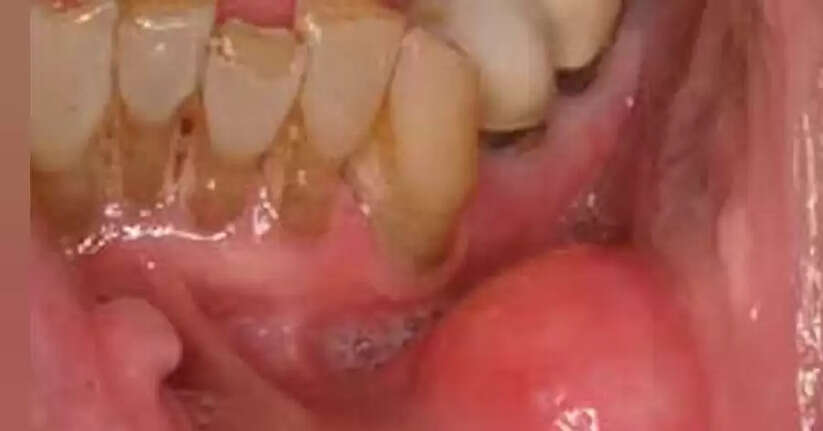

ഇഞ്ചിയിൽ അടങ്ങിയിരിക്കുന്ന ജിഞ്ചറോൾസ് എന്ന സംയുക്തം നമ്മുടെ വായയിലുണ്ടാവുന്ന ബാക്ടീരിയകളുടെ വളർച്ച തടയുകയും വായസംബന്ധമായ അസുഖങ്ങൾ തടയുന്നതിനും സഹായിക്കുന്നു. എല്ലാ ദിവസവും പുതുതായി അരിഞ്ഞ ഇഞ്ചി വായിലിട്ട് ചവയ്ക്കുക, അല്ലെങ്കിൽ ഒരു കപ്പ് ഇഞ്ചി ചായ കുടിക്കുക. ഇങ്ങനെ ചെയ്യുന്നത് വായിലുണ്ടാവുന്ന വരള്ച്ച ഇല്ലാതാക്കാനും ആരോഗ്യത്തോടെ ഇരിക്കാനും സഹായിക്കുന്നു.